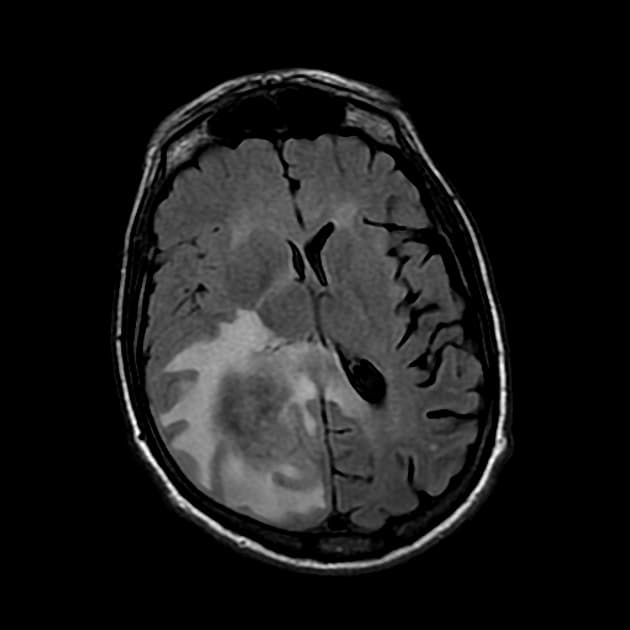

Axial T2

Phát hiện nhiều nốt (nodule) ở nhu mô não vùng đại não (cerebrum) và tiểu não (cerebellum), cả hai bên, trong đó tổn thương lớn nhất nằm ở thùy thái dương phải (temporal lobe), kích thước khoảng 17 × 16 mm.

Có phù vận mạch (vasogenic edema) quanh tổn thương. Tổn thương có tín hiệu không đồng nhất (heterogeneous signal intensity): chủ yếu giảm tín hiệu (hypointense) trên hình ảnh T1W, tăng tín hiệu (hyperintense) trên T2W và FLAIR, kèm theo hạn chế khuếch tán nhẹ (mild diffusion restriction).

Trên hình ảnh SWI, thấy các vùng giảm tín hiệu (hypointensities) rải rác, tương ứng với tăng tín hiệu trên hình ảnh pha (Phase imaging) – gợi ý xuất huyết (suggestive of haemorrhage).

Sau tiêm thuốc cản quang, tổn thương cho thấy tăng quang mạnh, không đồng nhất (strong, heterogeneous enhancement).